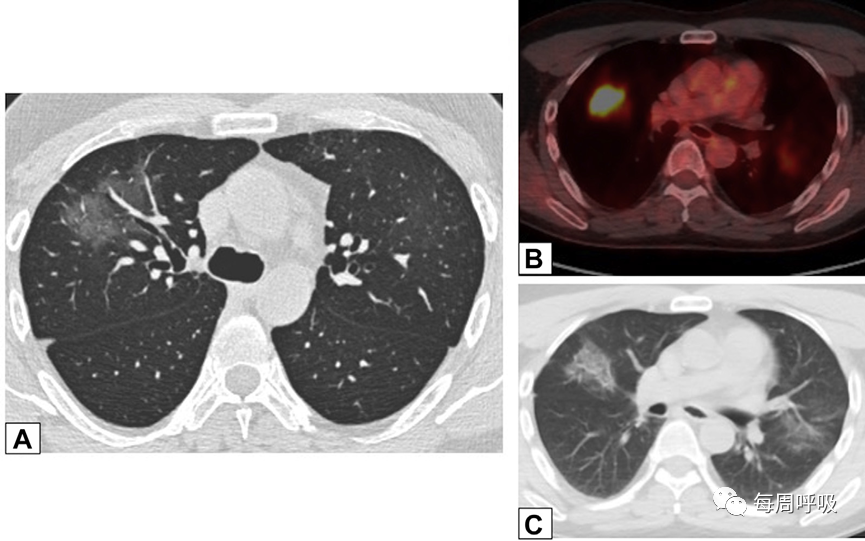

图7 A-C,磨玻璃影(GGO)A,一名有甲状腺乳头状癌病史的47岁男性,碘131治疗4个月后的轴位CT平扫图像,显示右肺上叶支气管血管周围的GGO。PET/CT扫描显示GGO代谢增高(B),轴位CT平扫图像显示左肺上叶新出现的较小GGO区域活动减弱(C)。经支气管活检结果与机化性肺炎相符。

图8 铺路征。一名71岁男性因使用胺碘酮导致继发性机化性肺炎的轴位(A)和冠状位(B) CT平扫左肺广泛磨玻璃影,小叶间隔增厚和小叶间隔增厚(铺路石)。